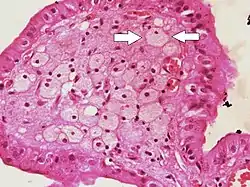

| Micrograph of cholesterolosis of the gallbladder, with an annotated foam cell. H&E stain. | |

The name strawberry gallbladder comes from the typically stippled appearance of the mucosal surface on gross examination, which resembles a strawberry. Cholesterolosis results from abnormal deposits of cholesterol esters in macrophages within the lamina propria (foam cells) and in mucosal epithelium. The gallbladder may be affected in a patchy localized form or in a diffuse form. The diffuse form macroscopically appears as a bright red mucosa with yellow mottling (due to lipid), hence the term strawberry gallbladder. It is not tied to cholelithiasis (gallstones) or cholecystitis (inflammation of the gallbladder).[2]